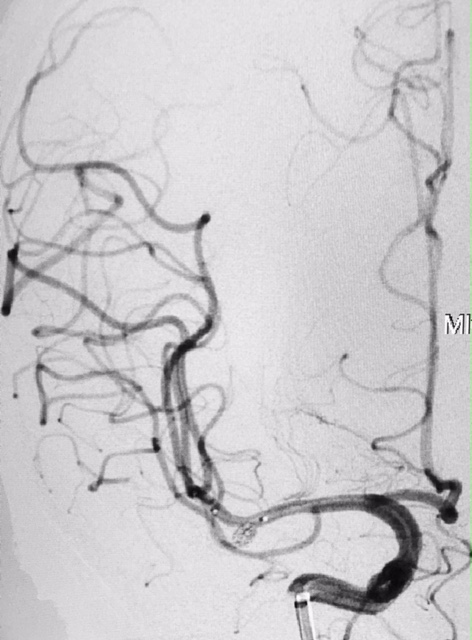

Tratamento de aneurisma cerebral com auxílio de balão duplo lumém e neurostent LEO